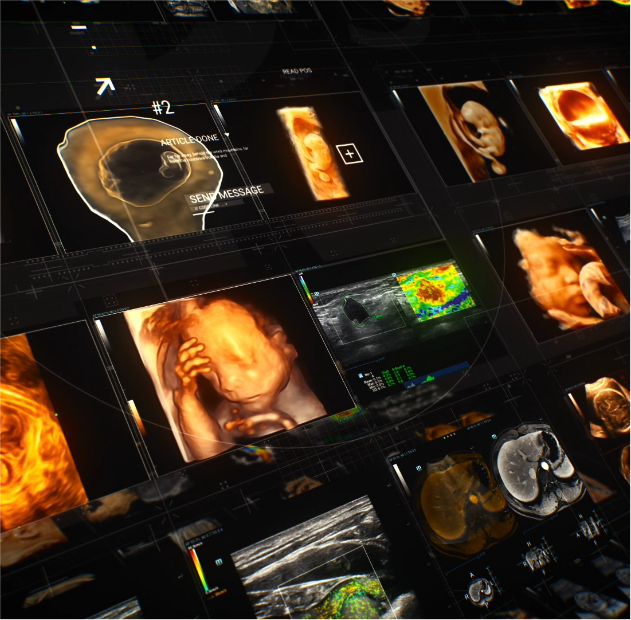

OptimizaciĂłn del rendimiento clĂnico y los resultados de los pacientes

Ayudando a los hospitales a crear beneficios de gran escala